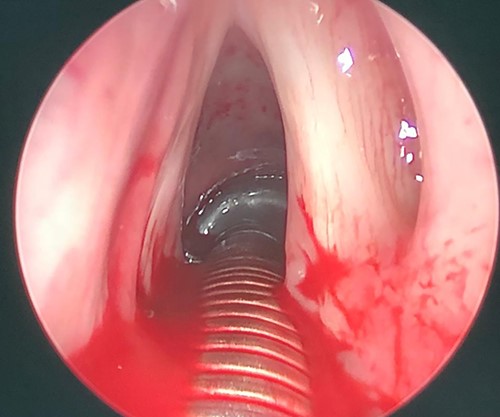

Patient was booked for direct laryngobronchoscopy with left false vocal cord mass excisional biopsy using Co2 laser. Examination under general anesthesia showed the mass extending from the left false vocal cord to the left ventricle (Figs 3 and 4). It measured 2 × 0.5 × 1 cm. The subglottic area was patent with no masses seen (Fig. 5). The mass was excised completely using Co2 laser aiding in patent airway (Fig. 6). Specimen was sent for histopathology.

Intraoperative picture, showing left sided mass originated from left false vocal fold.